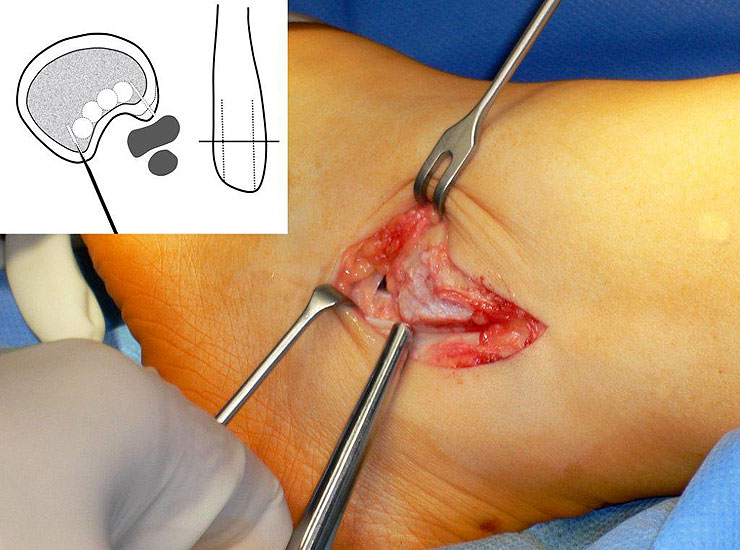

Die Peroneus brevis und die Peroneus longus Sehne verlaufen normalerweise hinter der Fibula (Abbildung 1). Neben der Gleitrinne an der Fibularückfläche sorgt das Retinaculum peroneale und das Retinaculum extensorum für eine weitere Stabilisierung. Bei der Peronealsehnenluxation oder –Instabilität können verschiedene Formen unterschieden werden (Abbildung 2):

• Ggf. Magnetresonanztomographie des Rückfußes mit Kontrastmittel in Bauchlage und Plantarflexion des Fußes zur Beurteilung der Sehnen und des Bandapparates 20. Die Aussagekraft der MRT ist bezüglich gleichzeitiger Schäden der Sehnen gut. Die Instabilität selbst kann durch eine MRT Untersuchung nicht abschließend ausgeschlossen werden, da Untersuchung oft nicht im Stadium der akuten Luxation durchgeführt wird (Abbildung 3). Dagegen erlaubt die dynamische Untersuchung mit Ultraschall eine präzise Beurteilung der Sehnenstabilität 21.